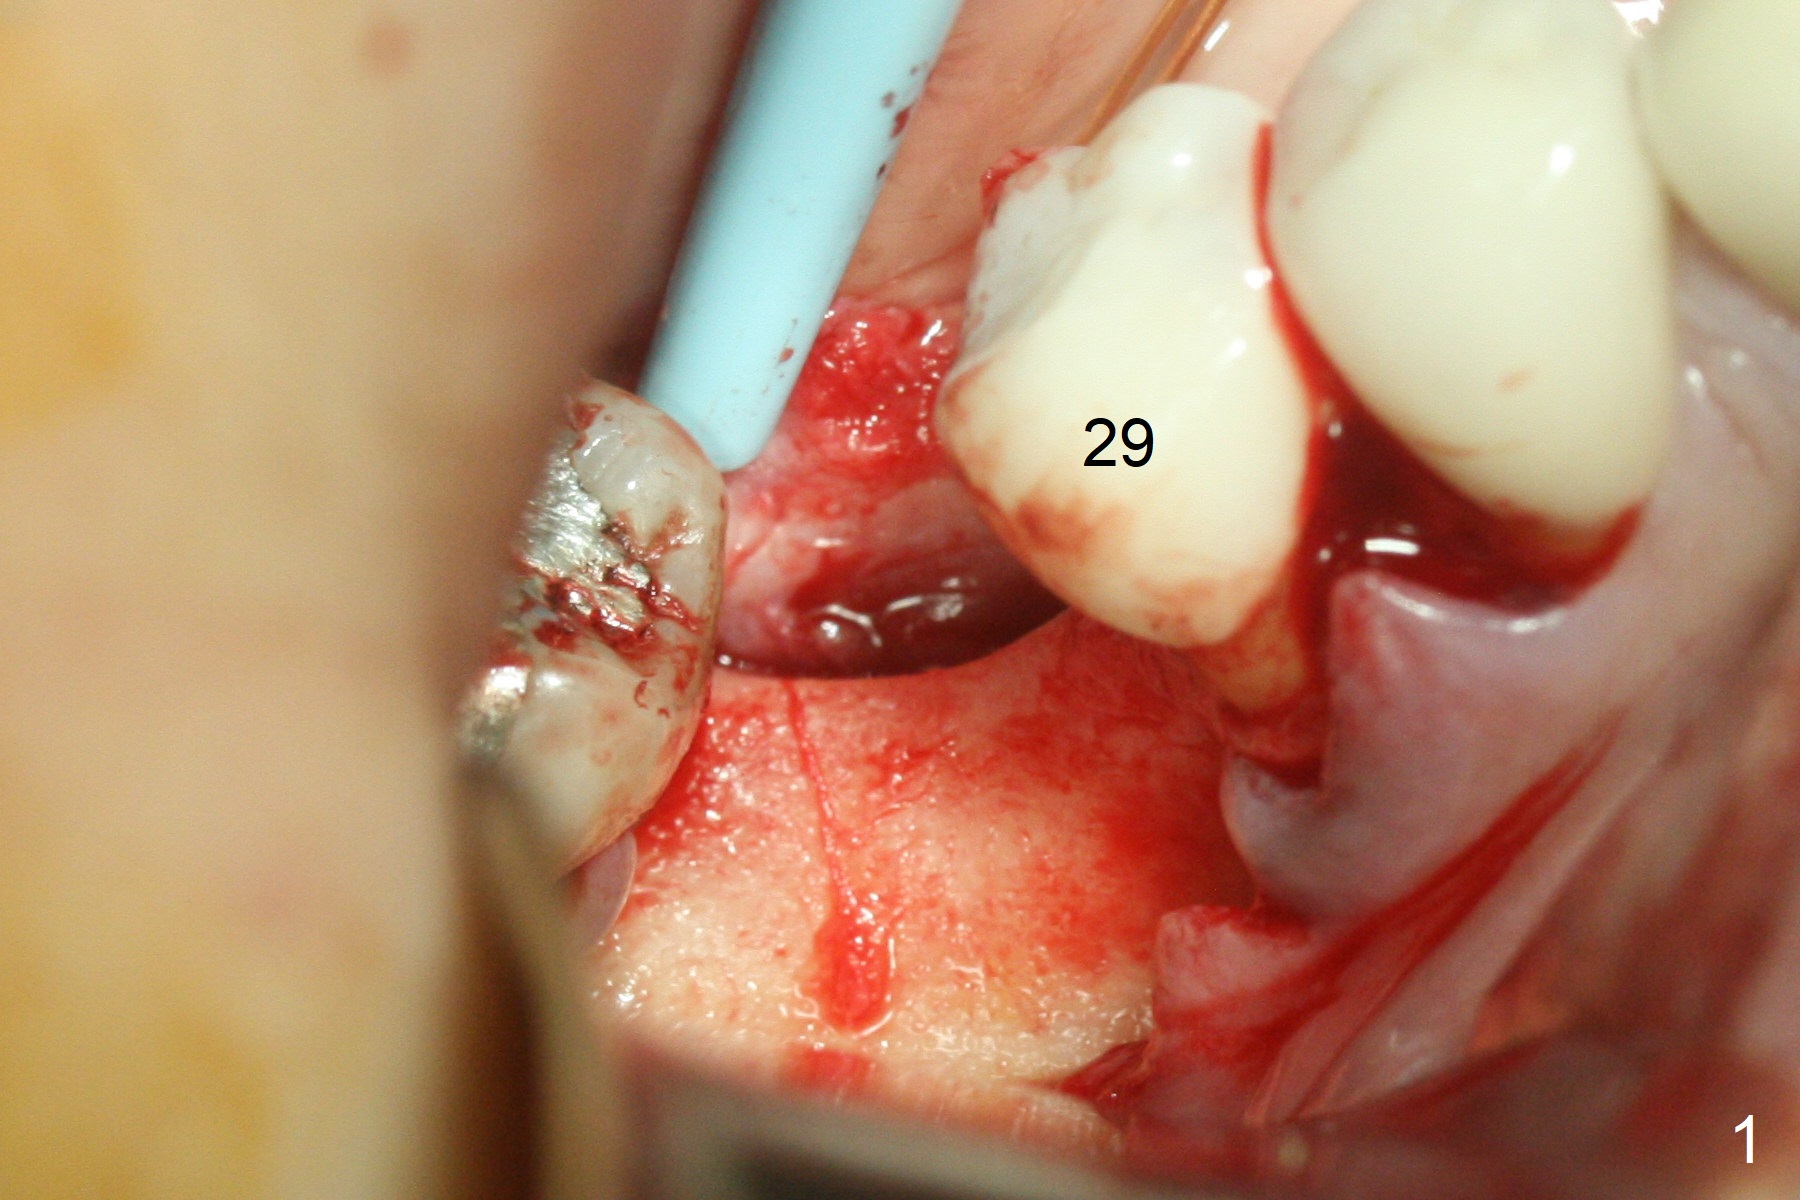

Incision reveals a narrow ridge and a narrow mesiodistal space at #30 (Fig.1). It seems that a 1-piece implant is indicated. Due to limited mouth opening, a 1.2 mm drill is unstable in place after use for 10 mm; instead a 1.5 mm drill is able to be inserted for 8 mm (Fig.2). A 3x10(2) mm 1-piece dummy implant is placed with 40 Ncm at an apparently acceptable level (Fig.3 >). Clinically a few threads are exposed buccally. When a definitive implant with the same dimension is inserted with 45 Ncm, it looks seated too deep (Fig.4,5). The latter is noted after suturing. The implant is backed up for a few turns so that the length of the abutment appears a little more reasonable. Introspectively, a 4 mm cuff should have been used after ridge reduction. Although there is no bone loss 4 months postop (Fig.6), the abutment margin (Fig.7 arrow) is subgingival (red dashed line: gingival margin). Diode laser is used for gingivectomy prior to impression. The bone density around the implant increases 11 months post cementation (Fig.8 *), probably related to recurrent #18 infection. The patient uses floss after meal.